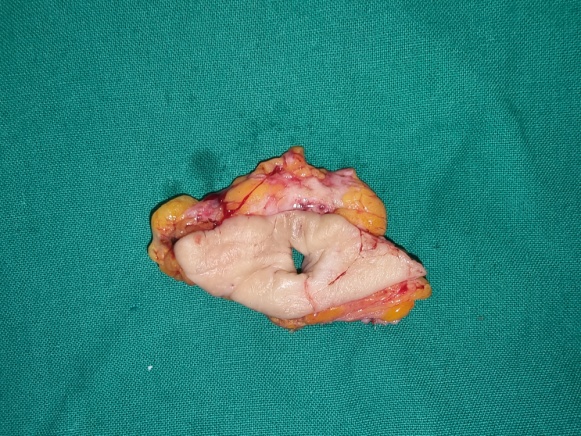

Το εξαιρεθέν ίνωμα. Παρατηρείται λευκή, ομοιογενής, ινώδης μάζα (Ευγενική παραχώρηση Dr. V. Penopoulos)